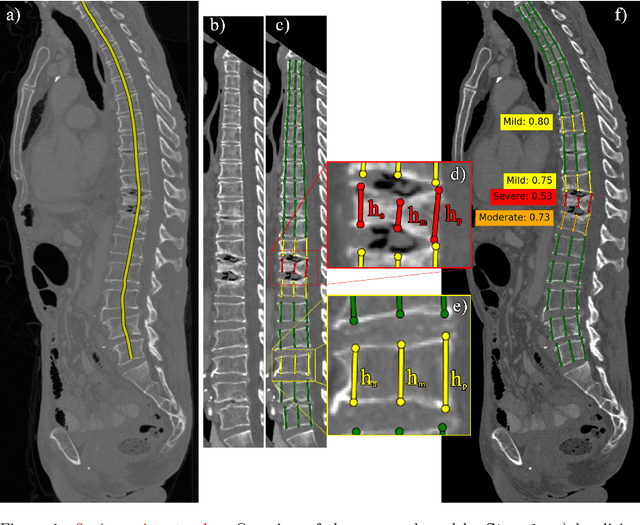

Abstract:Vertebral body compression fractures are early signs of osteoporosis. Though these fractures are visible on Computed Tomography (CT) images, they are frequently missed by radiologists in clinical settings. Prior research on automatic methods of vertebral fracture classification proves its reliable quality; however, existing methods provide hard-to-interpret outputs and sometimes fail to process cases with severe abnormalities such as highly pathological vertebrae or scoliosis. We propose a new two-step algorithm to localize the vertebral column in 3D CT images and then detect individual vertebrae and quantify fractures in 2D simultaneously. We train neural networks for both steps using a simple 6-keypoints based annotation scheme, which corresponds precisely to the current clinical recommendation. Our algorithm has no exclusion criteria, processes 3D CT in 2 seconds on a single GPU, and provides an interpretable and verifiable output. The method approaches expert-level performance and demonstrates state-of-the-art results in vertebrae 3D localization (the average error is 1 mm), vertebrae 2D detection (precision and recall are 0.99), and fracture identification (ROC AUC at the patient level is up to 0.96). Our anchor-free vertebra detection network shows excellent generalizability on a new domain by achieving ROC AUC 0.95, sensitivity 0.85, specificity 0.9 on a challenging VerSe dataset with many unseen vertebra types.

Abstract:Vertebral body compression fractures are reliable early signs of osteoporosis. Though these fractures are visible on Computed Tomography (CT) images, they are frequently missed by radiologists in clinical settings. Prior research on automatic methods of vertebral fracture classification proves its reliable quality; however, existing methods provide hard-to-interpret outputs and sometimes fail to process cases with severe abnormalities such as highly pathological vertebrae or scoliosis. We propose a new two-step algorithm to localize the vertebral column in 3D CT images and then to simultaneously detect individual vertebrae and quantify fractures in 2D. We train neural networks for both steps using a simple 6-keypoints based annotation scheme, which corresponds precisely to current medical recommendation. Our algorithm has no exclusion criteria, processes 3D CT in 2 seconds on a single GPU, and provides an intuitive and verifiable output. The method approaches expert-level performance and demonstrates state-of-the-art results in vertebrae 3D localization (the average error is 1 mm), vertebrae 2D detection (precision is 0.99, recall is 1), and fracture identification (ROC AUC at the patient level is 0.93).